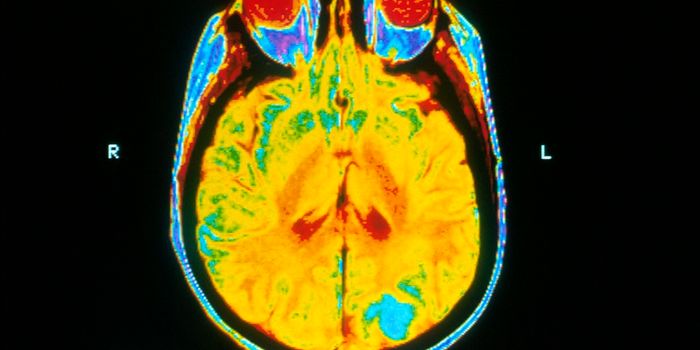

Read the latest articles about newly released neuroscience research and advances in experimental techniques. Topics include research news in neuroscience, neurology, psychology, brain science and cognitive sciences.